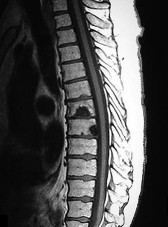

Question 8:

A 65-year-old male presents with classic symptoms of neurogenic claudication. He reports bilateral leg pain and fatigue that worsens with walking but is reliably relieved by leaning forward onto a shopping cart. In the pathogenesis of degenerative lumbar spinal stenosis, which structure is primarily responsible for dynamic central canal compression during spinal extension?

Correct Answer: Ligamentum flavum

Explanation:

In degenerative lumbar spinal stenosis, extension of the spine decreases the sagittal diameter of the canal because the ligamentum flavum buckles inward (shingling), dynamically compressing the thecal sac. Flexion of the spine pulls the ligamentum flavum taut, increasing the available canal space and alleviating neurogenic claudication symptoms. Hypertrophic ligamentum flavum is a major structural contributor to central stenosis.